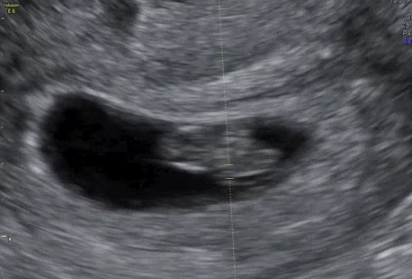

초음파에서 본 1.17cm의 아기, 그리고 처음 들은 심장소리

7주차에는 병원에서 아기집과 태아의 형태를 더욱 분명하게 확인할 수 있습니다.

저는 이번 주 초음파에서 아기의 크기가 1.17cm라는 이야기를 들었고, 작은 콩알 같은 그 모습에 눈물이 왈칵 쏟아질 뻔했어요.

하지만 진짜 감동은 심장소리를 듣는 순간이었습니다.'

작고 규칙적으로 ‘두근두근’ 울리는 소리를 듣는 순간, 아기가 실제로 제 안에 존재하고 있다는 사실이 온몸으로 와 닿았죠.